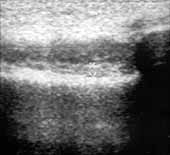

передняя крестовидная связка (Рис. 4). Наличие гиперэхогенных включений

передней крестовидной связки свидетельствует о ее кальцинозе (лигаментозе) (Рис.

5). Данное положение датчика позволяет визуализировать суставной хрящ латерального

и медиального мыщелков (Рис. 6), изменения формы суставных поверхностей

Рис. 4. Коленный сустав в норме. Поднадколенниковая область,

сагиттальная проекция; 1(+) — собственная связка надколенника, 2

— поднадколенниковое жировое тело, 3 — поднадколенниковая синовиальнакя

складка, 4(+) — передняя крестовидная связка.

Рис. 6. Коленный сустав в норме. Поднадколенниковая область,

сагиттальная проекция; гиалиновый хрящ медиального мыщелка бедренной

кости в норме (+).